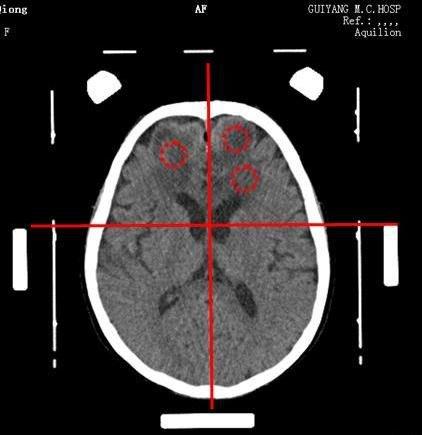

最初,蔣阿姨以為是抑郁、焦慮癥復發,接受住院治療,癥狀不見好轉,院方考慮其兩年前因宮頸癌進行過子宮、卵巢切除術,采取 CT、核磁共振掃描,在其顱內發現多個病灶,涉及左右大腦、小腦等,懷疑宮頸癌顱內轉移。

患者年齡大,曾經有子宮頸癌病史,影像發現中樞神經系統多發性占位性病變 …… 醫生考慮惡性病變,不排除轉移瘤,也認為有淋巴瘤的可能性,但難以確診,經試驗性治療后未見好轉,蔣阿姨轉入貴州醫科大學附屬醫院就診。

" 鑒于患者高齡,顱內發現多個病灶且具備轉移性病灶的特點,加之又有宮頸癌病史,存在重度水腫,構成‘小病灶大水腫’格局,我認為腦轉移瘤的可能性高。" 討論過半,貴醫附院神經外科專家拋出觀點,得到影像學家認可。

現代腦立體定向技術是一種新型診療手段,需將腦立體定向儀戴在病人頭上,由它來形成一個三維空間坐標體系,使腦部結構包括在這個坐標體系內,隨即送病人進行 CT 或核磁共振的掃描,就會得到帶有坐標參數標記的病人顱腦 CT 或核磁共振的圖像,病人顱腦內的各個影像解剖結構都會在這個坐標體系內有一個相應的坐標值,然后通過腦立體定向儀的機械數據來達到該坐標點,從而實現腦立體定向手術診斷治療疾病的目的。

" 目前,腦立體定向儀手術的精準度是在 1 毫米左右,靶向定位非常準確。" 伍國鋒教授表示,手術時找到 " 靶點 ",把穿刺針組件在立體定向儀導向器引導下,經電鉆驅動刺穿顱骨,繼而用探針緩慢送入病灶中心,輕輕抽取可見的腦組織,再將其交由臨床病理科進行多種方法染色,最終確診為中樞神經系統 NKT 細胞淋巴瘤。